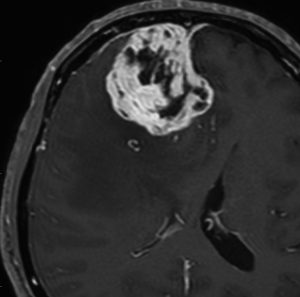

angiomatous meningioma WHO grade 1 血管腫様髄膜腫

術前検査ではまるで膠芽腫のような画像です。でも,開けてみれば髄膜腫ということはすぐにわかる肉眼所見です。硬膜の至る所から腫瘍血管が流入して出血性腫瘍です。

多数の小血管から構成される組織像です。右のvimentin染色は陽性です。

核小体明瞭な大小不同な類円形核からなる細胞境界が不明瞭な腫瘍細胞がみられ,ヘモジデリン貪食マクロファージも認められます。MIB-1染色率は2-3%でグレード1です。